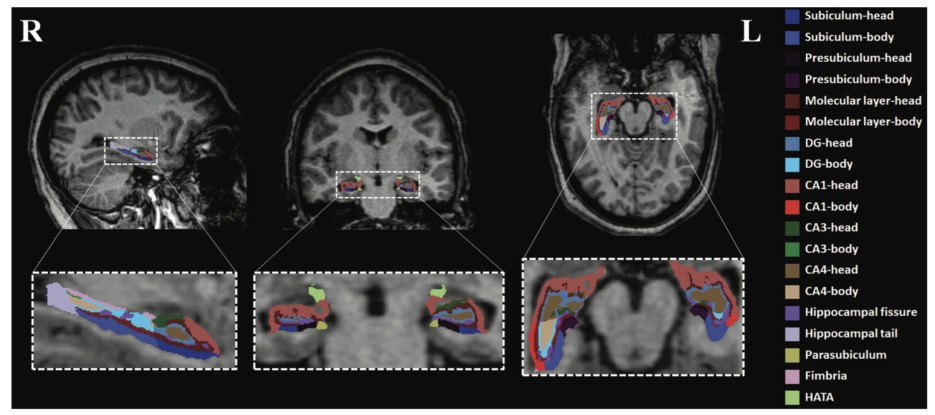

Mỗi người tham gia nghiên cứu đều được chụp cộng hưởng từ để kiểm tra cấu trúc của vỏ não và hồi hải mã. Đây là hai vùng não chịu trách nhiệm về sự tư duy cao cấp như đưa ra quyết định, học tập, ghi nhớ.

Ngoài ra, thể tích hồi hải mã ở trẻ bị ngưng thở khi ngủ lớn hơn người trong nhóm đối chứng. Độ chênh lệch tăng theo mức độ nghiêm trọng của chứng ngưng thở khi ngủ. Các nhà nghiên cứu cho biết điều này có thể do sưng và viêm trong não.

Hồi hải mã ở một bé gái 12 tuổi mắc chứng ngưng thở khi ngủ. Ảnh: Sleep.